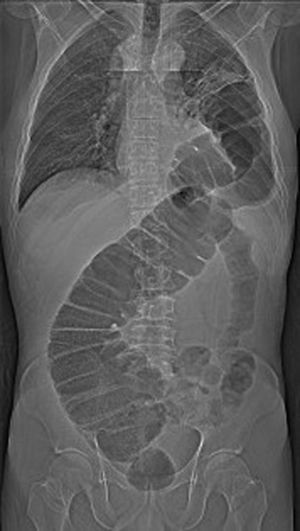

The patient is a 51-year-old male who had undergone robotic Ivor-Lewis esophagectomy with manual anastomosis and hiatal closure around the gastric plasty. No postoperative complications were observed, and the patient was discharged after 11 days. Three days later, he came to the emergency room with sudden abdominal pain and vomiting. Thoracoabdominal radiography and CT scan revealed a transhiatal herniation of the colon with large retrograde dilation (Fig. 1). We decided to perform urgent laparoscopic surgery. After reducing the hernia content, the hiatal orifice was closed and a left chest tube was inserted. The patient evolved favorably and was discharged 4 days after hospitalization.